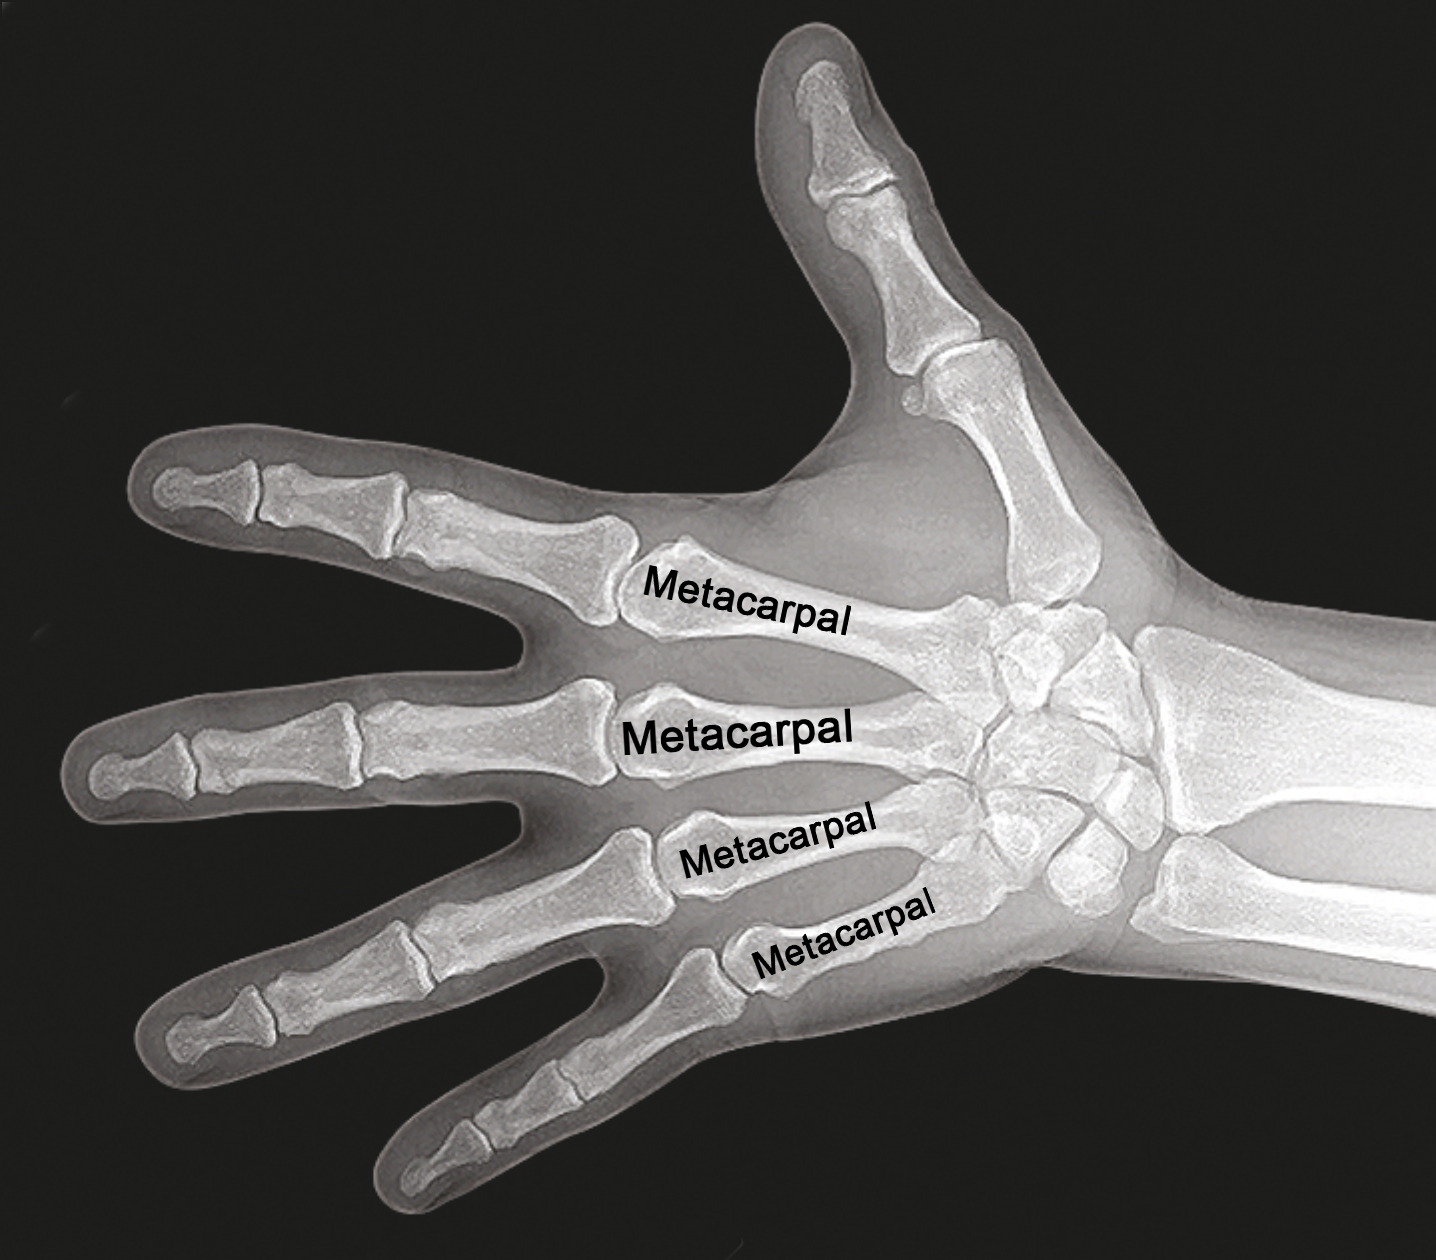

• Hand X-ray showing the index, long, ring, and little metacarpals.

Hand X-ray showing the index, long, ring, and little metacarpals.